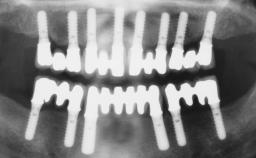

Immediate Loading of Six Implants in the Maxilla and Final Restoration with a Full-Arch CAD/CAM Zirconia FDP

# of Implants 6

Type of Implants One-Piece

Attachment One-Piece